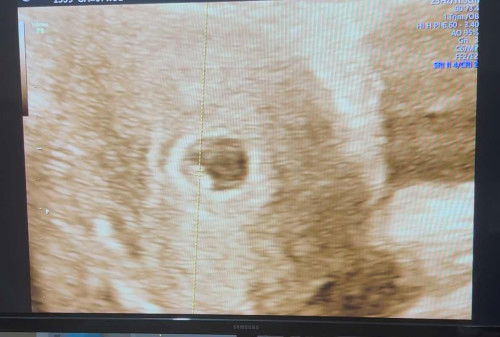

Hamil 6 minggu 4 hari baru terlihat kantungnya saja

Bun mau tanya disini ada yang udah usg kehamilannya di 6 minggu ngga? Saya tadi usg baru terlihat kantungnya saja blm terlihat janinnya